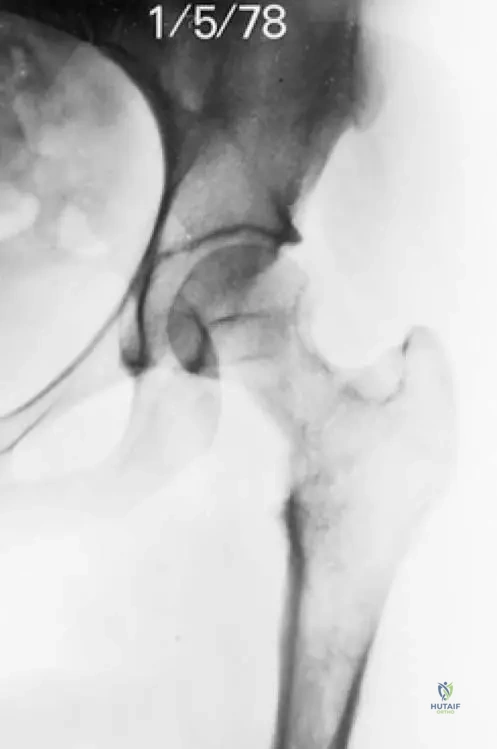

A 60-year-old patient presents with chronic hip pain. Radiographs show significant lytic destruction in the proximal femur with concentric narrowing of the femoral neck, as depicted in the image. This finding is characteristic of which aspect of Gorham's disease?

View Answer & Explanation

Correct Answer: C

Rationale: The image (Fig. 8.57) shows "Lytic destruction in the proximal femur with concentric narrowing of the femoral neck," which is a direct visual representation of the "massive, progressive osteolytic changes" that define Gorham's disease. Main Distractor: Option B, malignant bone tumor infiltration, is incorrect. While it can cause lytic lesions, Gorham's disease is a benign vascular process, and the pathology explicitly states no cytological atypia, ruling out malignancy.